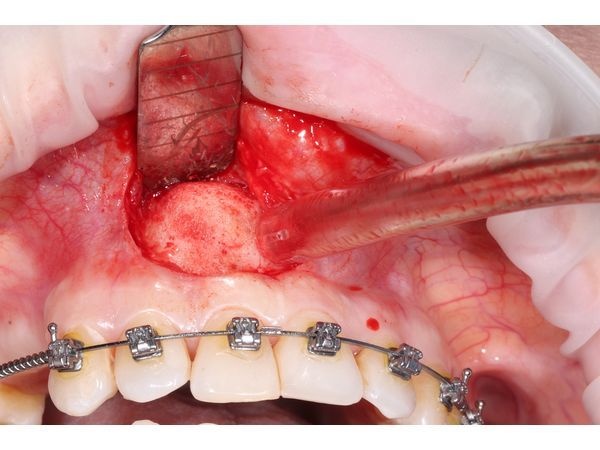

- пинцетом аккуратно извлекли кисту вместе с оболочкой и остатками пломбировочного материала за верхушкой корня;

- удалили верхушку корня и запломбировали оставшуюся верхнюю часть Триоксидентом;